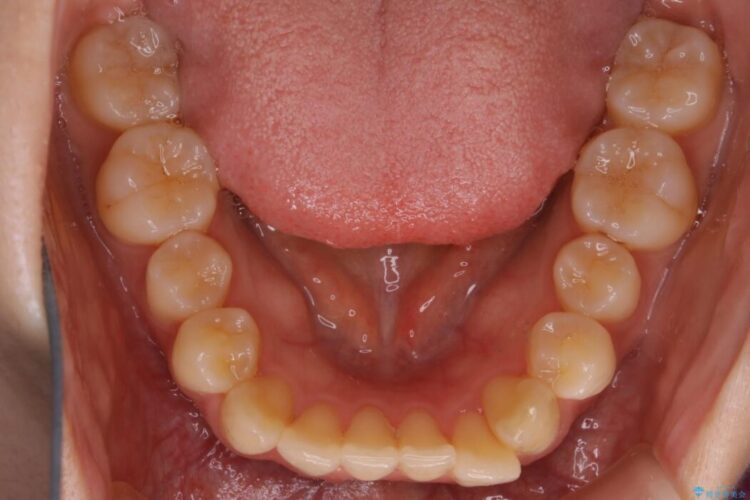

下の前歯のガタつきが気になるとご来院された患者様です。

インビザラインのライトパッケージにて、歯列拡大とディスキング(IPR)をを行いスペースをつくり非抜歯で治療を行いました。